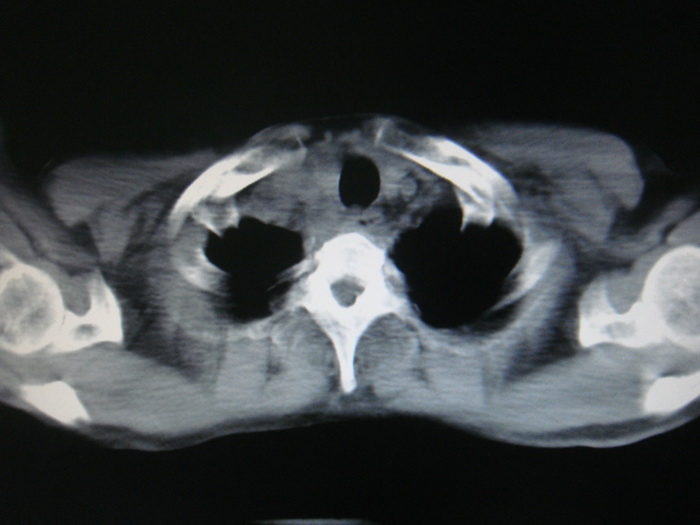

标题: CT28366:男性,45岁,偶尔发现右颈部肿块行胸部CT扫描。 [打印本页]

男性,45岁,偶尔发现右颈部肿块行胸部ct扫描。

颈部肿块也可能是转移。